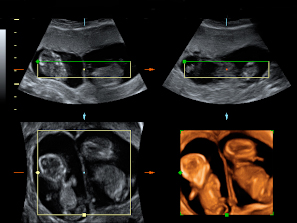

Ecografías de la semana 12: anomalías cromosómicas

Las anomalías cromosómicas se producen cuando hay alguna alteración en los 46 cromosomas del bebé (23 heredados del padre y otros 23 de la madre). El riesgo aumenta con la edad de la madre, sobre todo a partir de los 35 años. Muchas cromosomopatías se detectan a través de la ecografía de la semana 12.